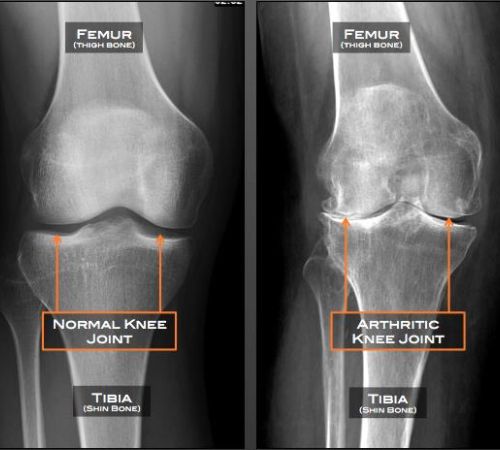

Αποτελεί μια εκφυλιστικού τύπου αρθρίτιδα της άρθρωσης του γόνατος. Με την πάροδο του χρόνου προκαλείται παραμόρφωση της αρθρικής επιφάνειας του γόνατος.

Η κλινική εικόνα συνίσταται σε χωλότητα βάδισης με σύνοδο άλγος, σύγκαμψη της άρθρωσης καθώς και απώλεια του φυσιολογικού εύρους κίνησης. Το γόνατο παρουσιάζει διαταραχή του φυσιολογικού άξονα κίνησής του.

Η επιβεβαίωση της διάγνωσης γίνεται με απλή ακτινογραφία.